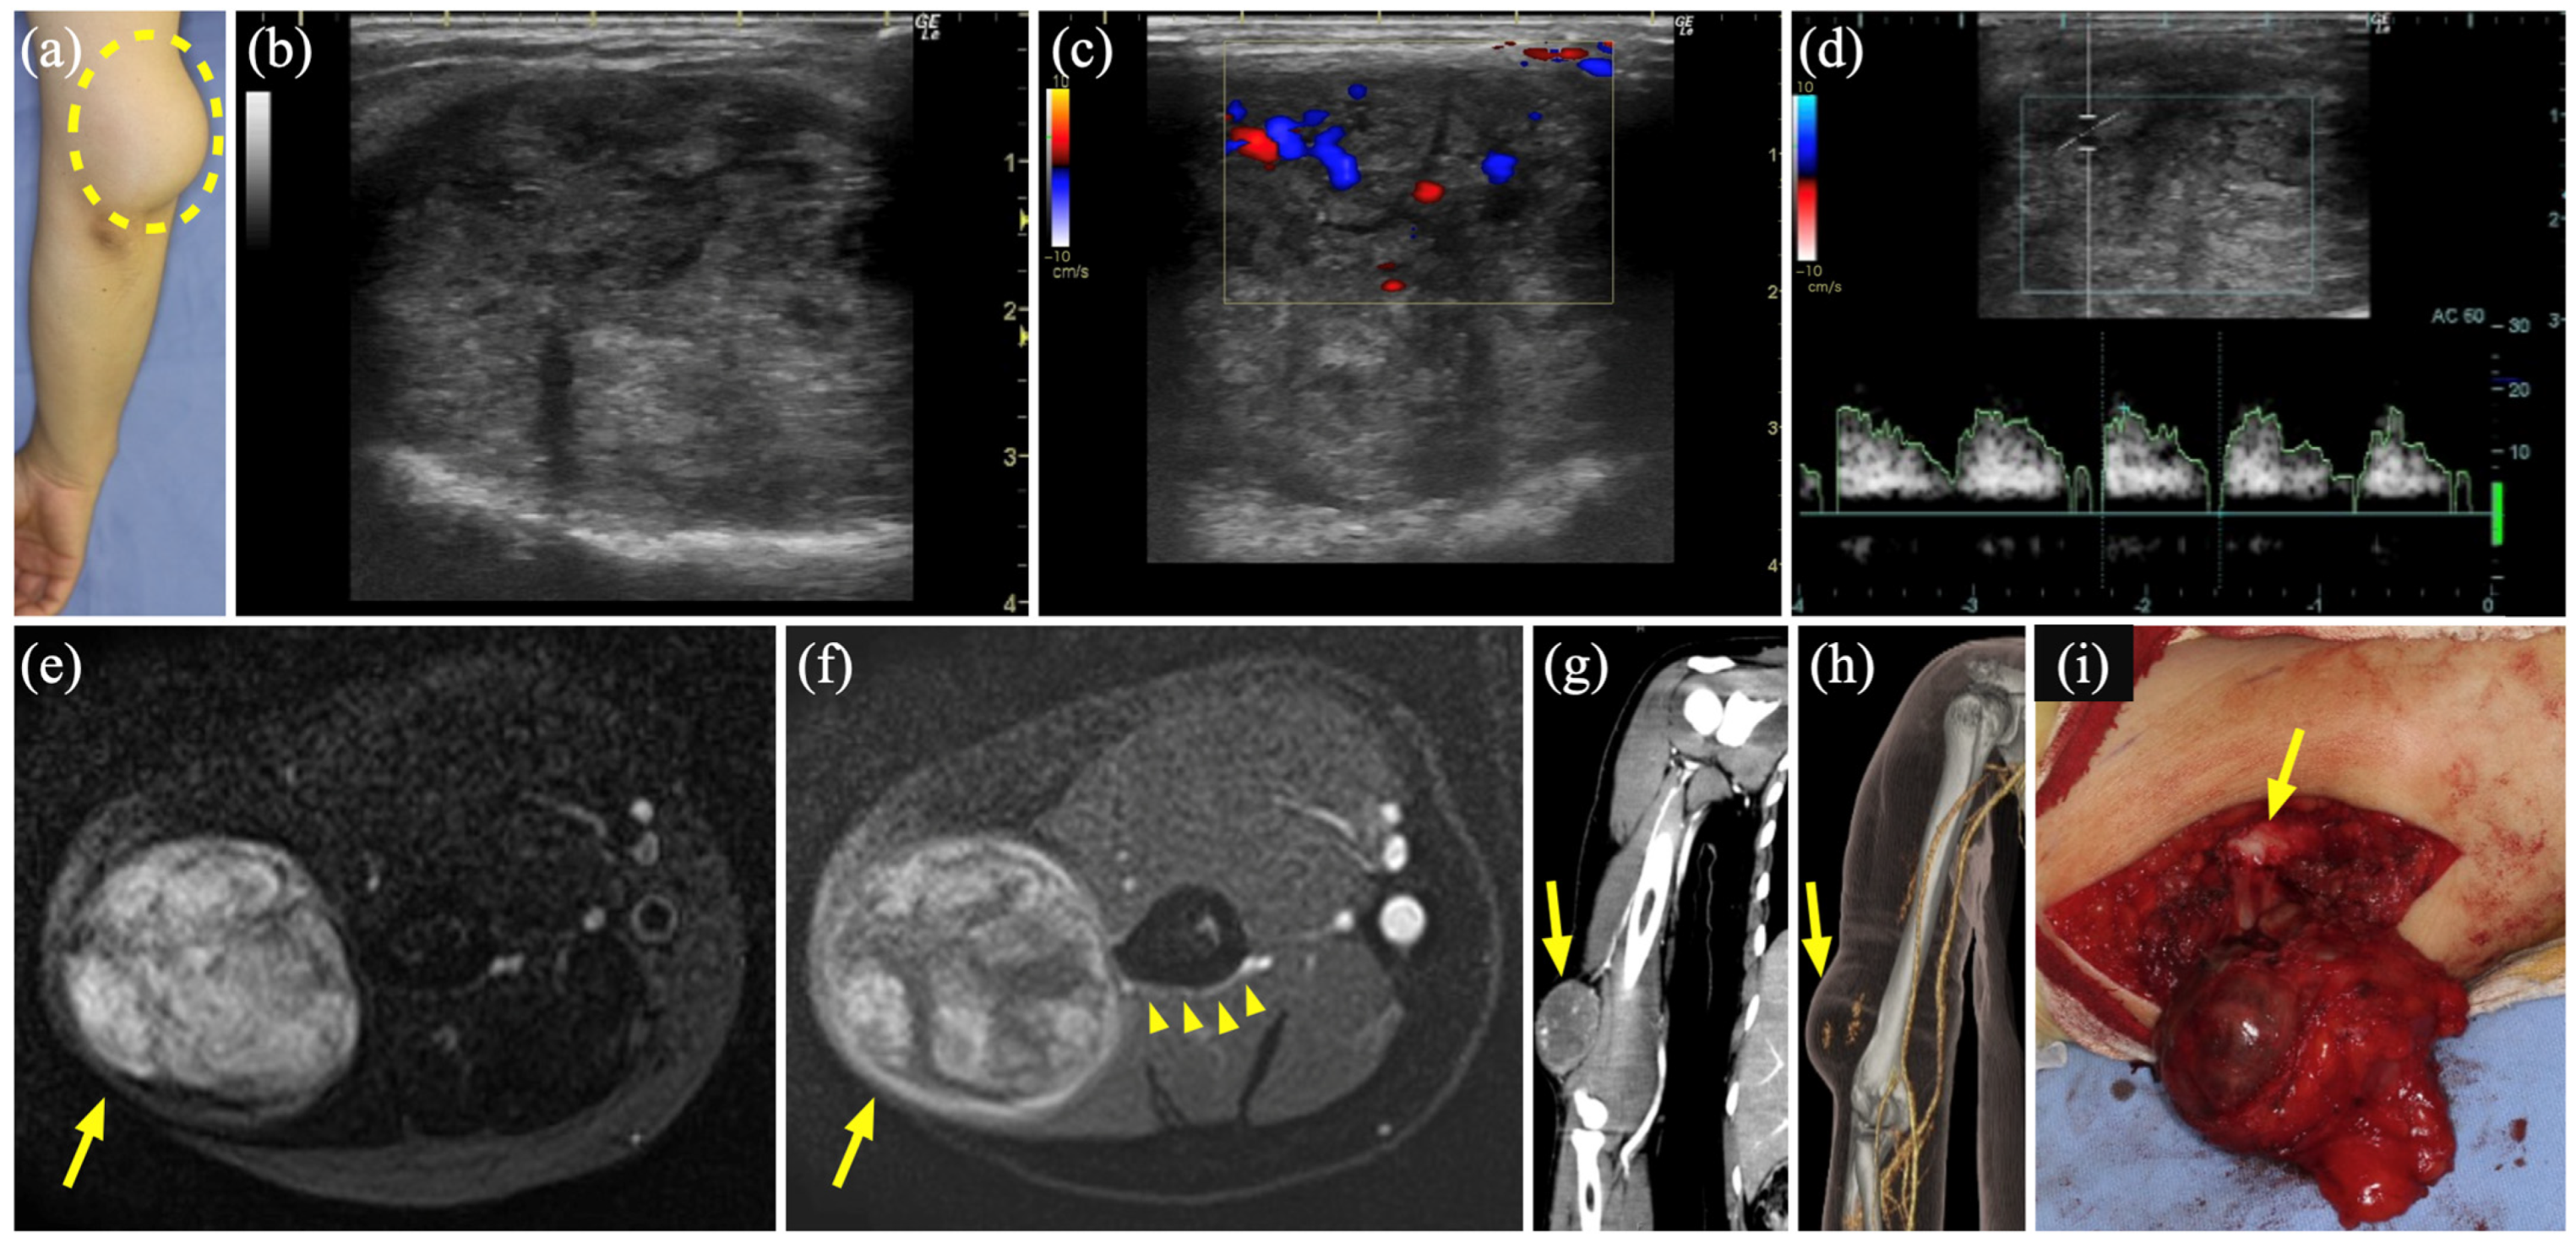

3.5. Case 4

| 4 | 39 | F | Rt upper arm | VM | US, MR, 3D-CTA | Sc, 1 time 2 biopsies | Schwannoma | 788 |